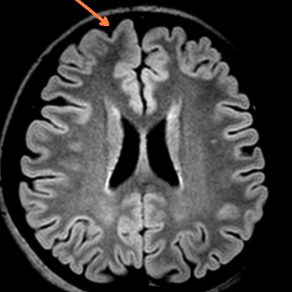

术前影像学评估(头颅MRI提示:考虑左侧额叶白质区点状缺血灶,但细看右额极似有脑发育不良,PET-CT提示右侧额极、扣带回低代谢